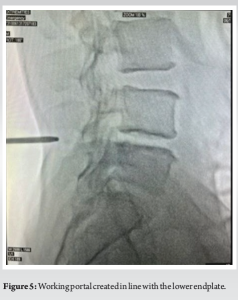

Once the patient is positioned and necessary trial imaging is done, the patient is draped and prepared for the procedure. The lateral position allows the surgeon the flexibility to either stand or sit during the surgery. Under C-arm guidance, midline and medial pedicular lines are marked (Fig. 4). Using a 30° scope, the working portal is made in line with the superior endplate of the lower vertebra (Fig. 5), and the viewing portal is placed 3 cm cranial to the working portal (Fig. 6). Once the portals are created, the working space is established at the spinolaminar junction with the aid of a blunt periosteum, shaver, and radiofrequency ablation (Fig. 7).